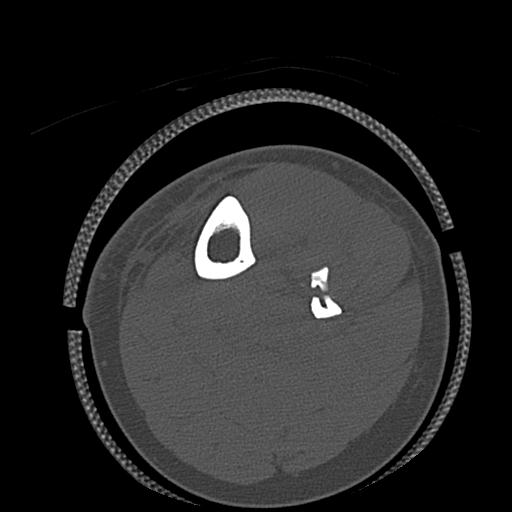

49554 3/13 膝 4R 3/16 4R 1/18 2R 78歳男性 膝蓋骨骨折